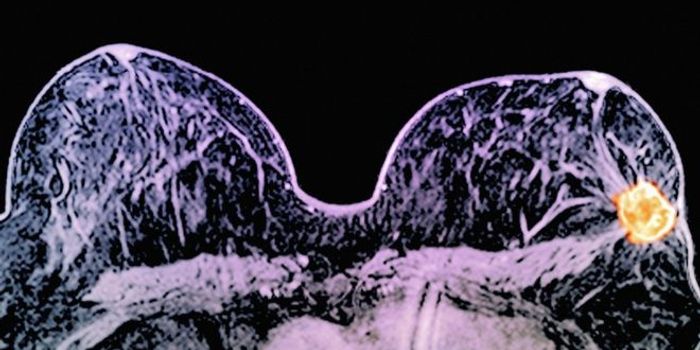

FEB 18, 2016Clinical & Molecular DXGenetic testing for BRCA1/2 mutations is on the rise in young women diagnosed with breast cancer. Researchers documented ...

AUG 25, 2023CancerOn this day in 1789, George Washington, the first President of the United States, lost his mother to breast cancer. ...

FEB 21, 2023CancerIn 1976, the American Cancer Society began to recommend mammograms, X-ray images of the breast, as a tool to diagnose br ...

MAR 14, 2016CancerIn a ground-breaking “surprise” finding, UK doctors announced a pair of drugs dramatically shrunk some breas ...